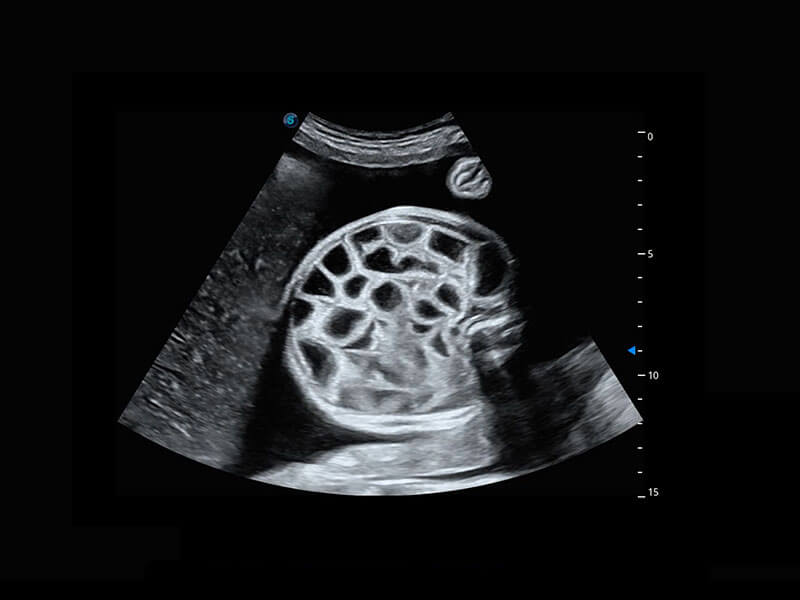

右室双出口